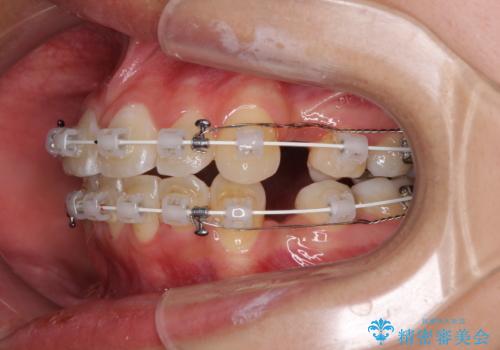

- 矯正装置

- 審美装置

- 上下前歯のデコボコと、それによる磨きづらさを気にして来院された患者様です。

叢生解消のため、上下左右第一小臼歯4本を抜歯し、ワイヤー装置にて矯正治療を行うこととしました。